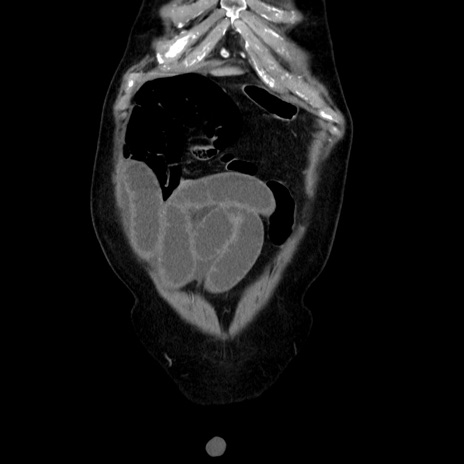

横断像